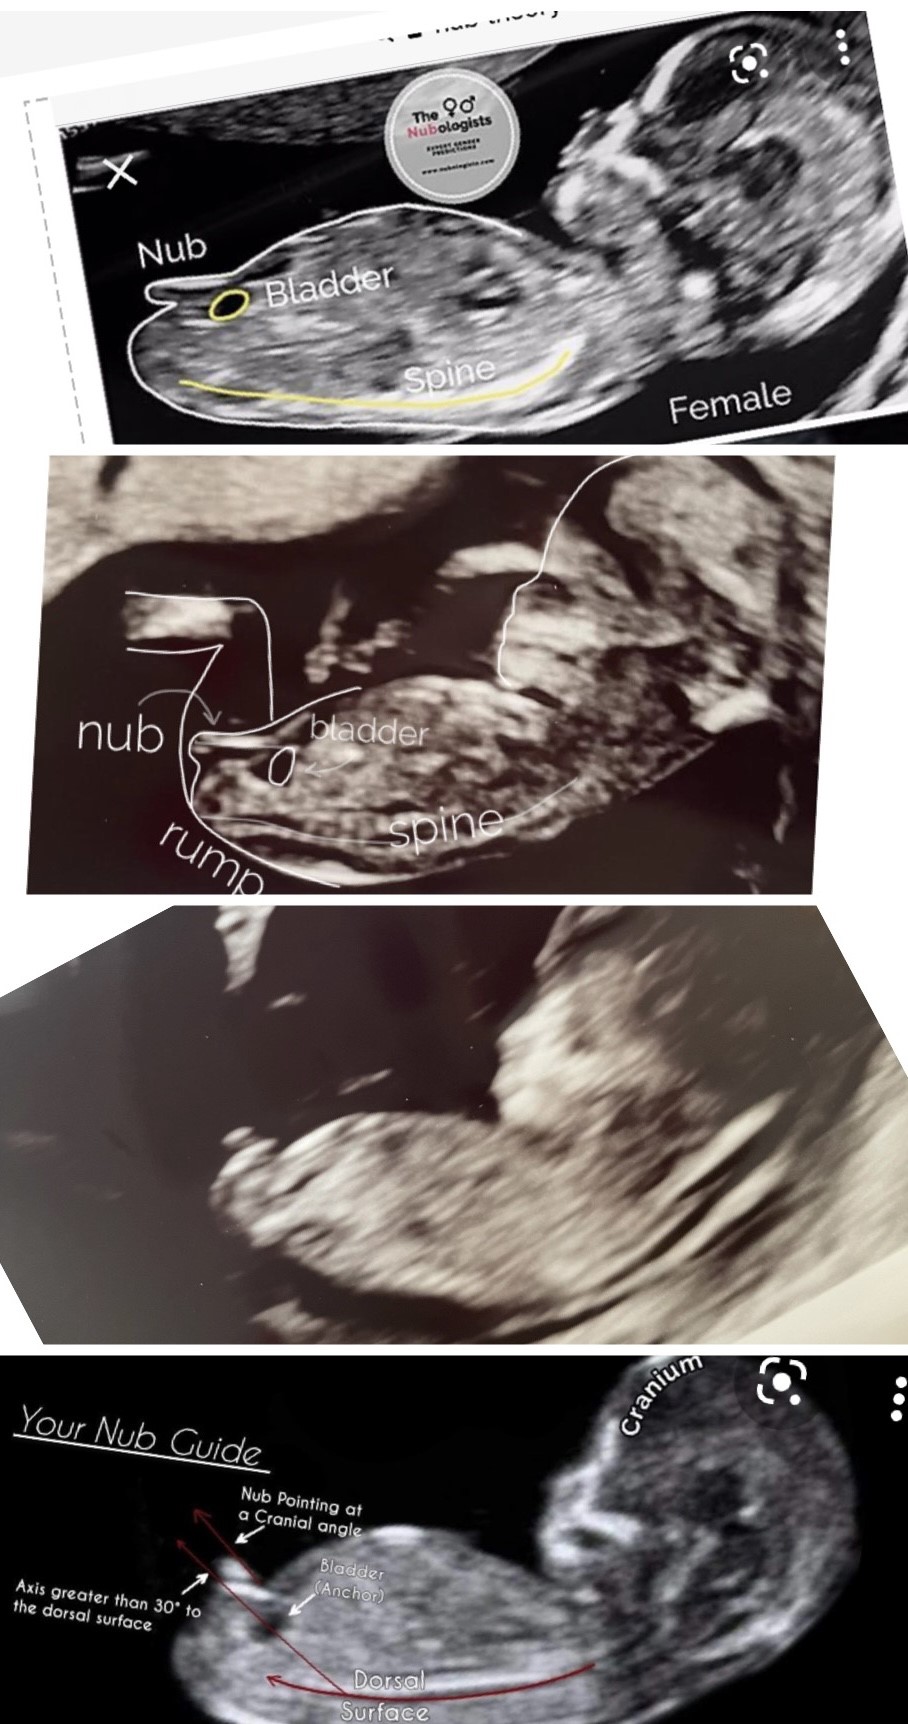

Eksperterne får ret gode anmeldelser på nettet, men jeg kan ikke forstå deres vurdering, som er 80 % pige.

De to midterste billeder er mine og det øverste og nederste er eksempler på nub-teorien. På det billede af mine, hvor eksperterne vurderer (og har tegnet), at det er en pige, kan jeg jo se en hvid prik ovenfor, som må være drengenubben? For ikke at tale om det andet, ret tydelige billede, som jeg også sendte til eksperterne.